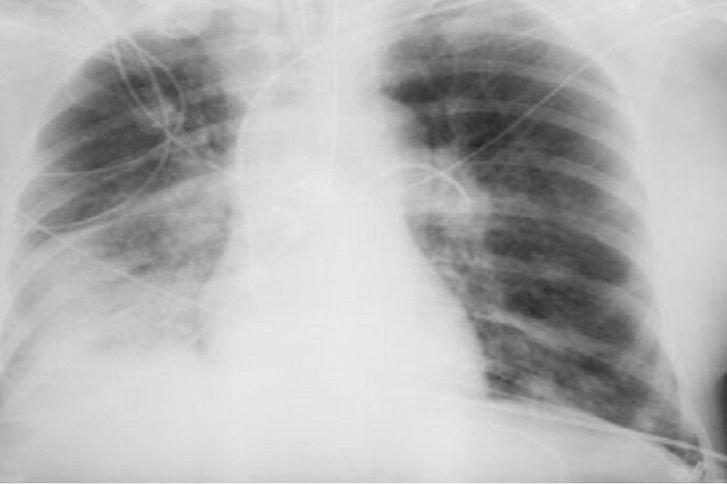

ووفقًا لها، يستخدم الإشعاع فقط في أنواع معينة من الفحوصات، ولا تتضمن جميع طرق التشخيص التعرض للإشعاع. فمثلاً، يستخدم التصوير بالموجات فوق الصوتية والتصوير بالرنين المغناطيسي، وهذه طرق آمنة تمامًا حتى للنساء الحوامل. أما الأشعة السينية فتستخدم فقط في التصوير الشعاعي، والتصوير الفلوري، والتصوير المقطعي المحوسب، بينما لا تتضمن طرق أخرى التعرض للإشعاع.

وتقول: "الأشعة السينية هي إشعاع كهرومغناطيسي، مثل الأشعة فوق البنفسجية والضوء والحرارة. صحيح قد تلحق جرعاتها العالية الضرر بالخلايا، كالذي تسببه حروق الشمس. وأن الاستلقاء تحت أشعة الشمس على الشاطئ دون حماية أخطر بكثير من تصوير بالأشعة السينية للصدر مرة واحدة سنويًا".

وتؤكد بلاتونوفا أن عدم اكتشاف المرض أخطر بكثير من الخضوع للأشعة السينية، حيث تقلل المعدات الحديثة من المخاطر، كما أن الفحوصات في الوقت المناسب تسمح بالكشف السريع عن الأمراض وبدء العلاج.